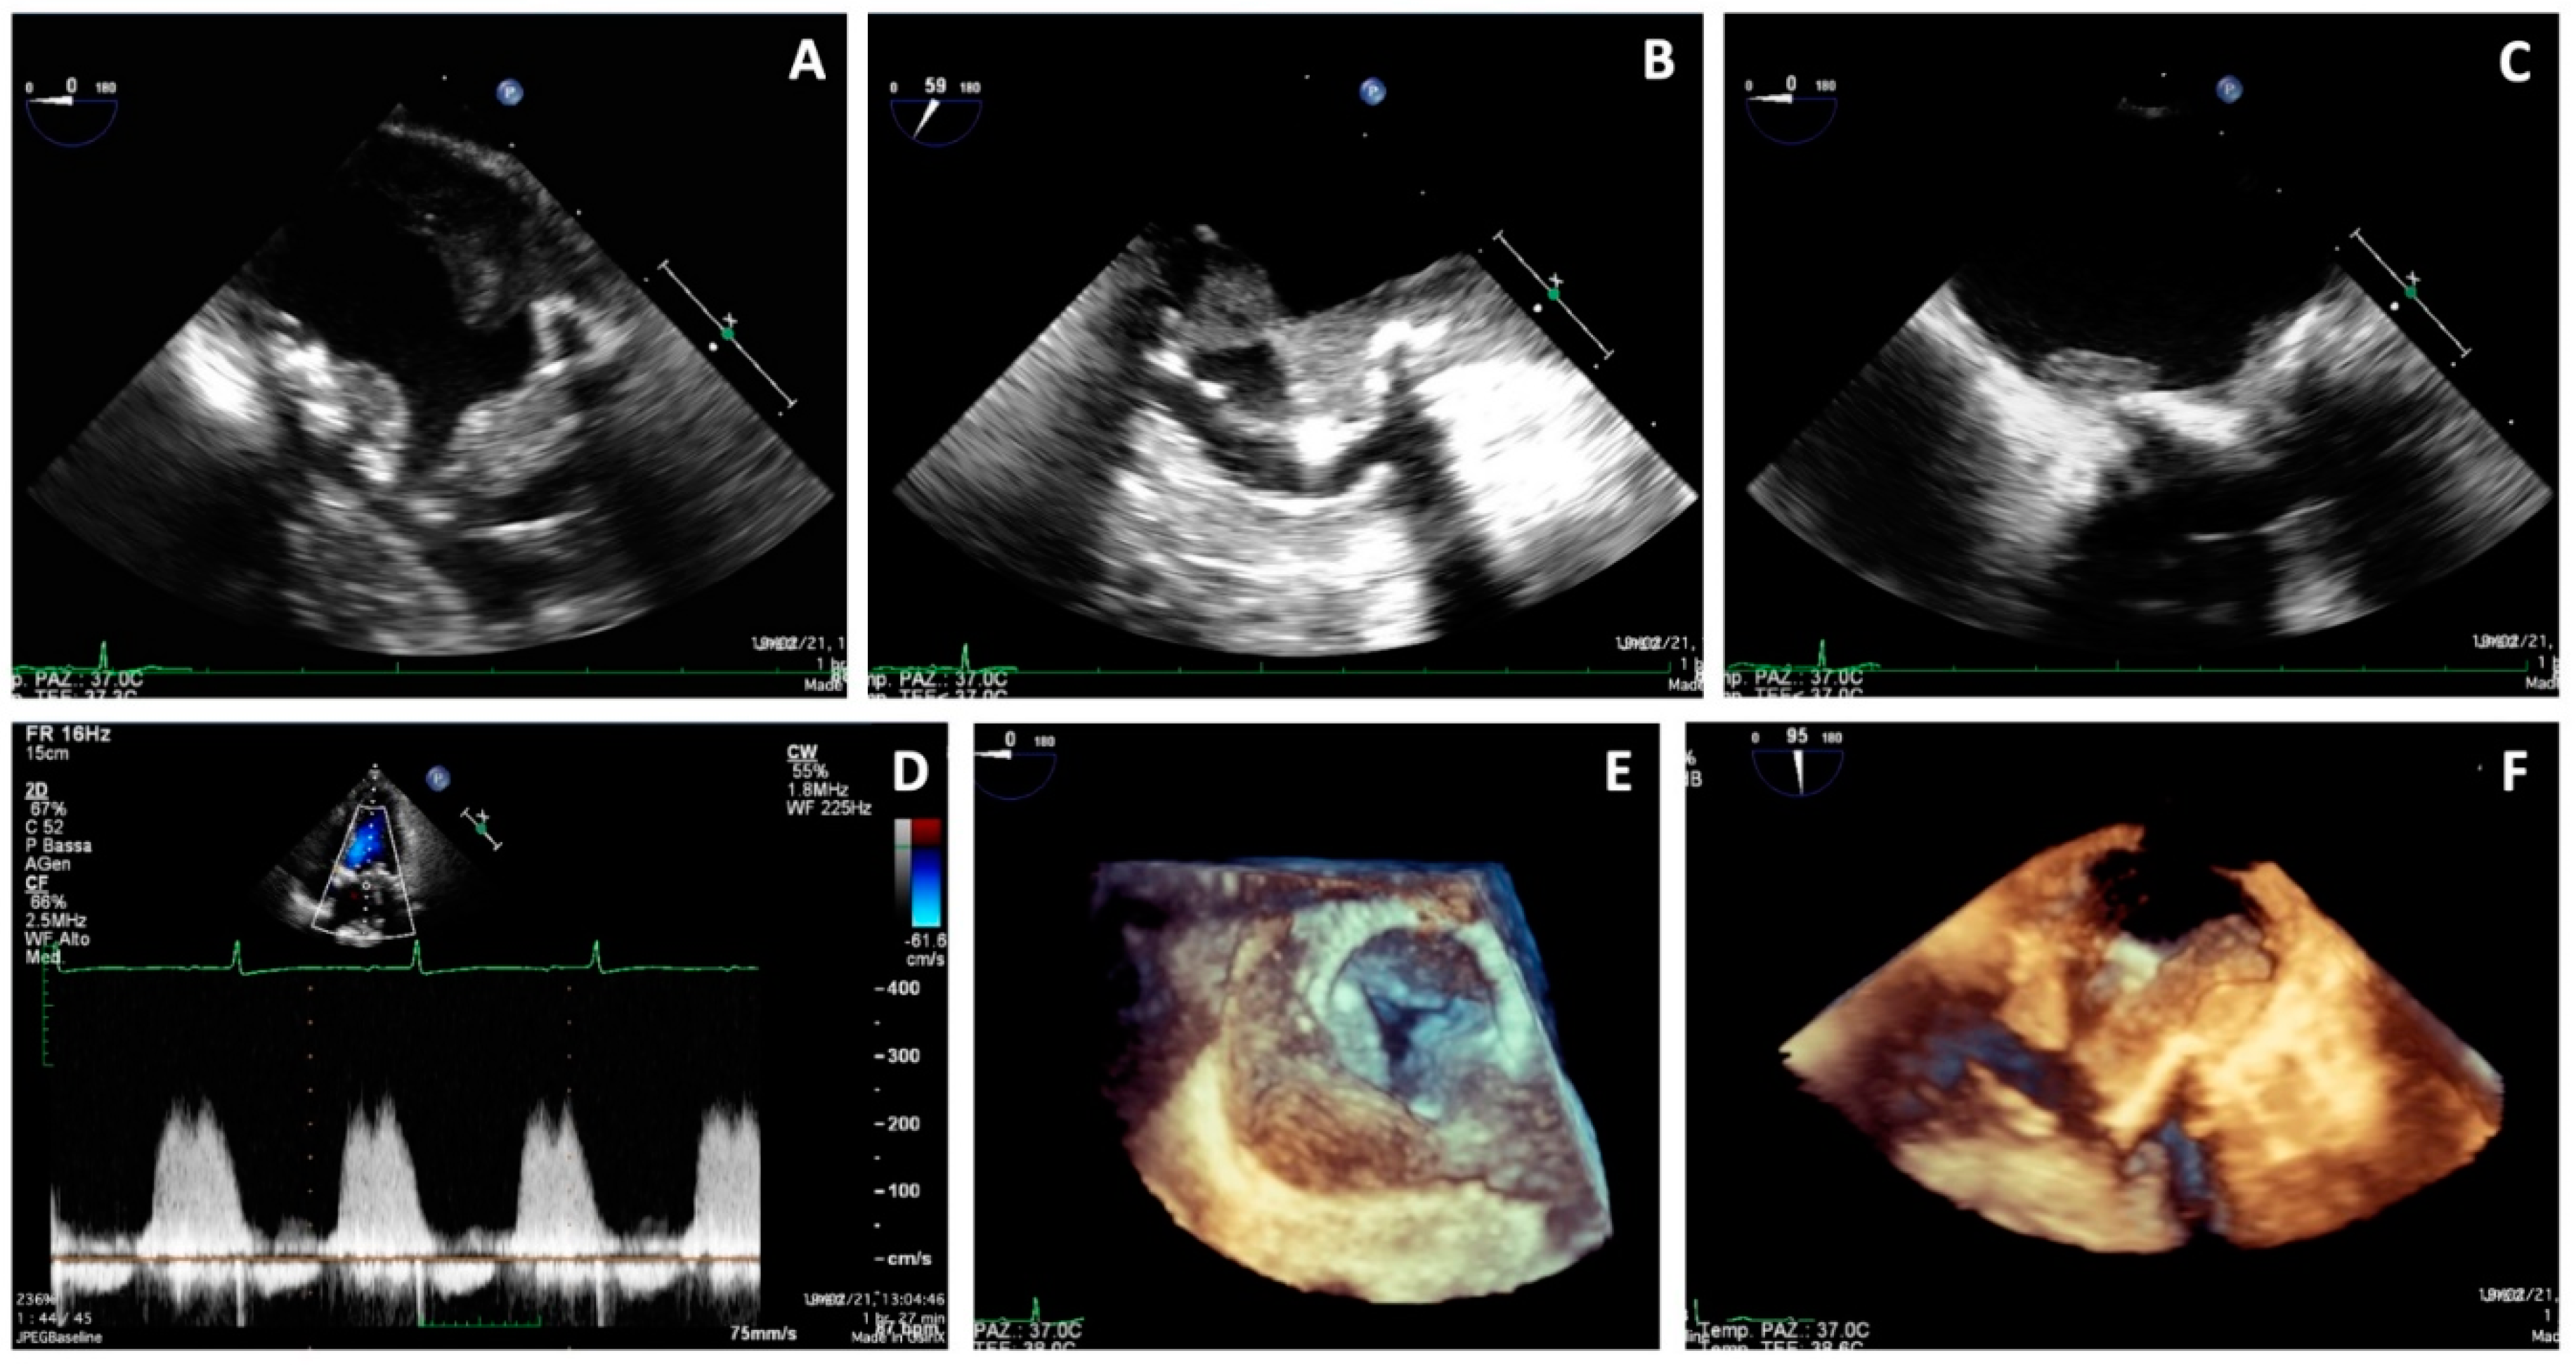

On 19 February 2021, the patient was referred to our center for a cardio-surgical assessment. At admission, the patient was in stable hemodynamic status andsymptomatic for dyspnea on minimal effort; however, she exhibited no orthopnea or resting dyspnea. The clinical assessment revealed the presence of diffuse ecchymosis, ischemia of the third toe of the right lower limb, and pulmonary basal rales; the EKG showed sinus tachycardia. Lab analysis showed an INR value of 3.5, normal renal function, increased white blood count with prevalence of neutrophils (14.280/μL, 82%), thrombocytopenia (50,000/μL), and 9-fold increase of D-Dimer (4.31 mg/L). A total-body CT scan excluded pulmonary embolism, revealed the presence of lung interstitial thickening and mild bilateral pleural effusion, and showed eccentric occlusive bilateral thrombosis of femoral veins, more prevalent on the right side; the cardiac phase showed extensive thrombotic stratifications in the left atrium (Figure 2). The TTE and TEE (Figure 3) showed mildly reduced systolic function (EF 50%) and gross and diffuse thrombosis of mitral prosthetic leaflets, prevalently on the ventricular side (thickness of approximately 1 cm), resulting in leaflet restriction and severe stenosis (mean gradient of 15 mmHg) with a severely reduced orifice area using 3D-guided planimetry (0.8 cm2). Moreover, a stratified thrombus (thickness of approximately 2 cm) was diffusely visible on the left atrial free wall. The aortic prosthesis had a mean gradient of 15 mmHg in the absence of thrombosis. The estimated systolic pulmonary artery pressure was 38 mmHg; an acceptable RV function (S’ 11 cm/s) was measured.

Figure 3. Transesophageal echocardiography showing massive thrombosis of mitral prosthetic leaflets, prevalently on the ventricular side, a stratified thrombus on the left atrial free wall (AC,F), increased gradients on the mitral prosthesis (D), and reduced orifice area at 3D en-face view (E).